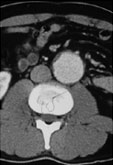

症例5

74歳 男性

検診異常, 間歇性跛行

【起始・経過】

かねてより、100mの間歇性跛行。

平成11年、腹部大動脈瘤を指摘された。

平成18年1月CTにて増大傾向を認め当院紹介受診。

AAA size 5.2 cm

【既往歴】

74歳 HCC→TAE

高血圧(+) 糖尿病(−) 喫煙歴(−)

【治療計画】

AAA stent graft(Cook Zenith) + Lt iliac stenting + Lt internal iliac embolization

Pre-operative CAT scan